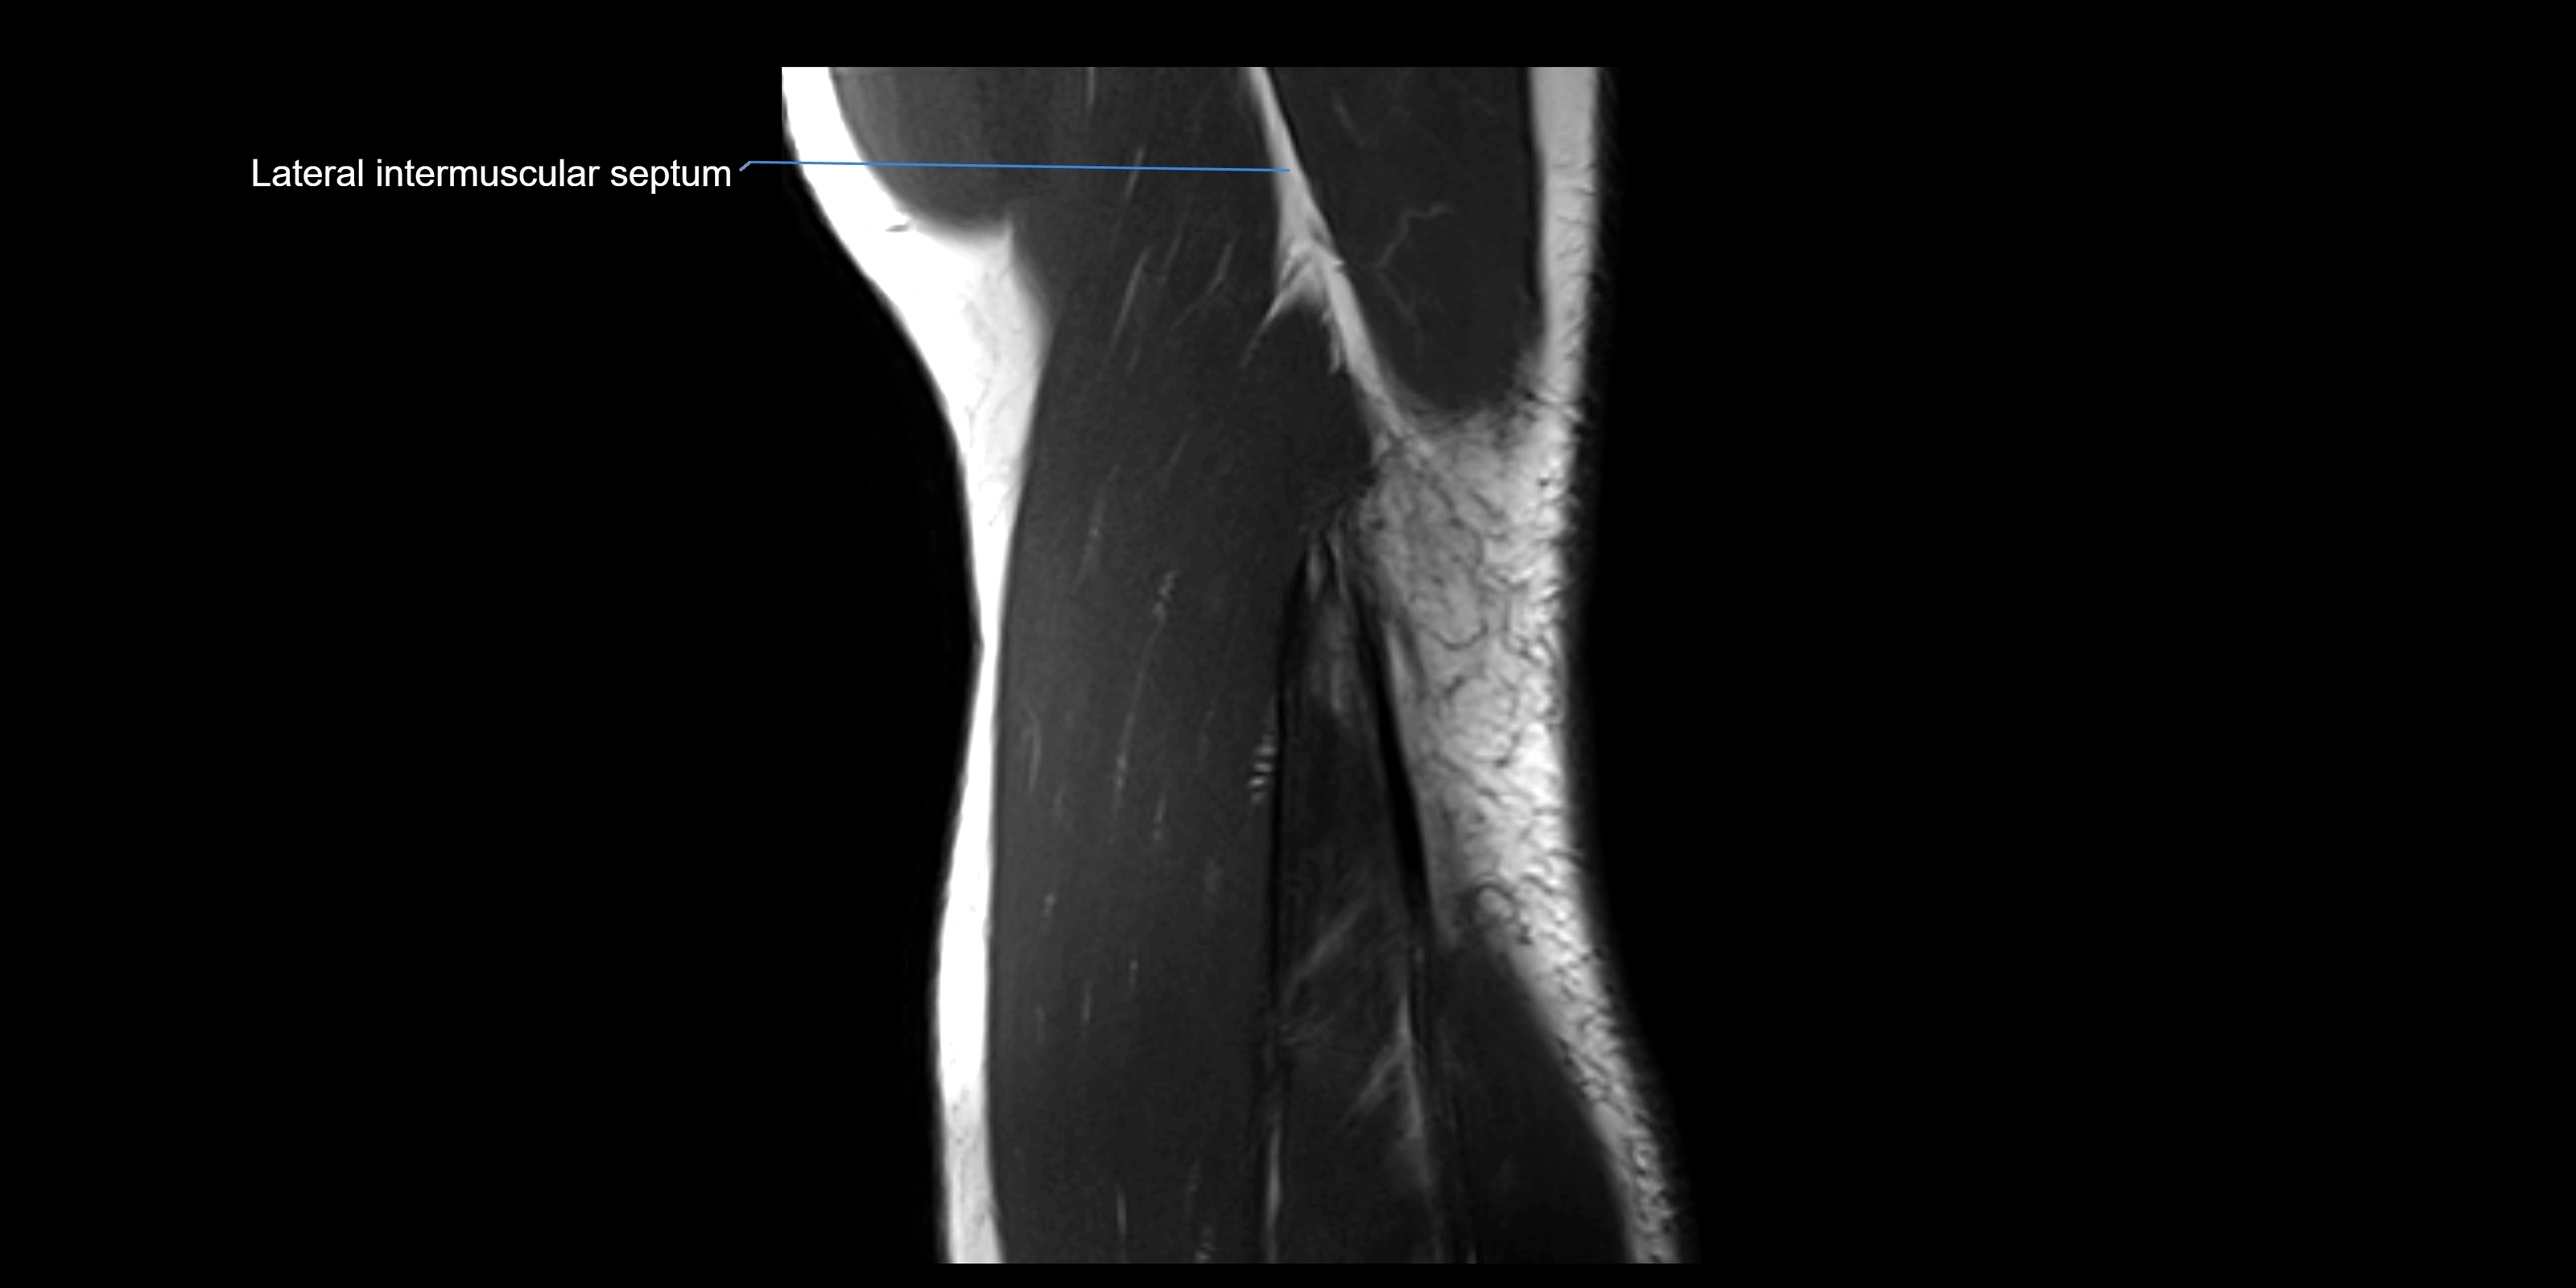

image